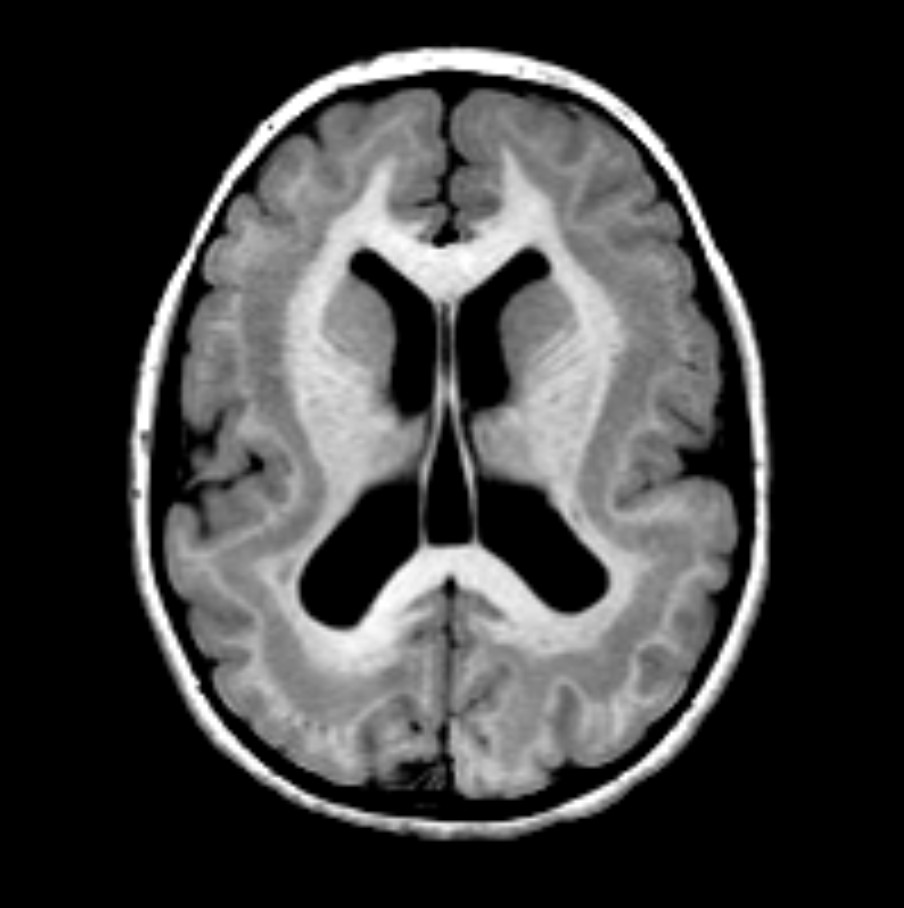

The life of a neuron involves many movements and morphological changes. Newborn neurons often migrate long distances to reach their final location in the developing brain. The neuron extends neurites, the axon generates a synapse, and the other neurites extend to form the complete neuritic arbor, which is pruned and reformed during development and learning. Brain development and function depend on the ability of neurons to accomplish these rearrangements. Each of these morphological changes require the active remodeling of the neuron's microtubule cytoskeleton. Each task is performed by microtubule associated proteins (MAPs). Misregulation or failure of MAPs causes a spectrum of disorders in brain development and neurodegenerative disease. Our lab studies the MAPs that cause these diseases. What do these MAPs do to microtubules and why do mutations cause disease? A current focus in the lab is the MAP doublecortin (DCX). Mutations in DCX cause an inherited form of epilepsy known as double cortex syndrome. Effective diagnosis, treatment planning, and drug development for these diseases requires a precise understanding of the molecular mechanisms underlying microtubule remodeling and MAP function in neurons.